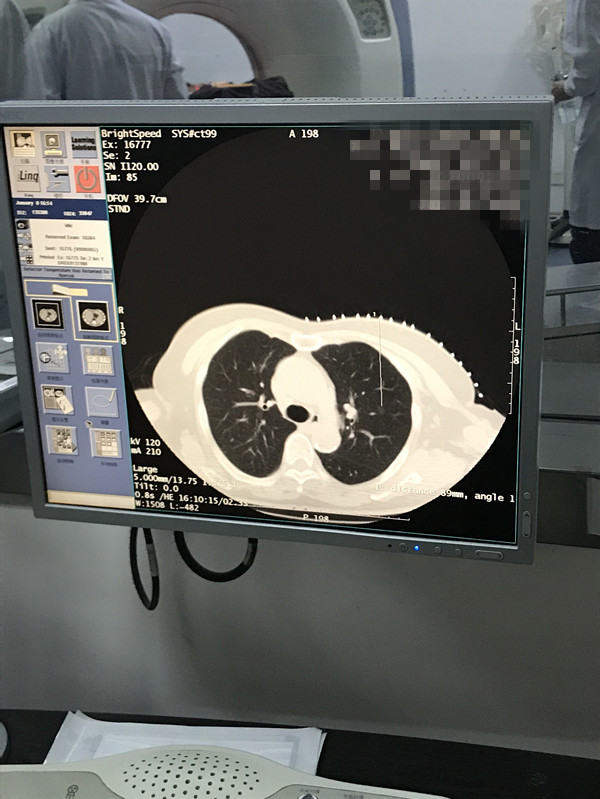

下一篇:2021年1月份肺部氩氦刀手术